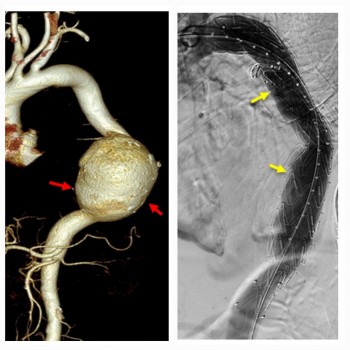

![]() Ngày 18/6, Bệnh viện Đa khoa quốc tế SIS Cần Thơ cho biết, các sĩ bệnh viện vừa can thiệp cấp cứu kịp thời cứu sống một bệnh nhân bị vỡ phình khổng lồ động mạch chủ bụng. |